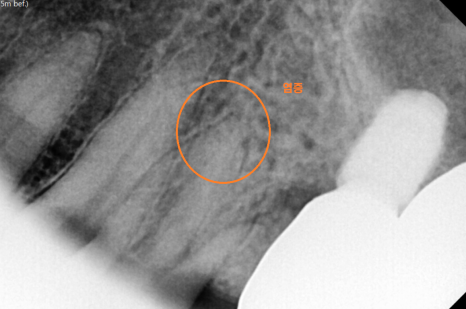

왼쪽이 시골 치과에서 약을 받아 먹었는데

계속 아파요

전남 완도에서 거주하고 계신 환자분

약을 먹어도 통증이 잡히지 않아

급하게 강일동 치과를 방문해주셨어요.

문제가 있어보이는 치아 2개

너무 아파서 발치를 원하셨습니다.

전남 완도 치과에서도

뽑아야한다 했는데

약을 먹고 버티고 계셨다 하셨습니다.

뿌리쪽 충치라 예후도 안좋고

염증으로 인하여 치아가 흔들려서

발치를 해야한다 환자분을 설득 드렸죠..